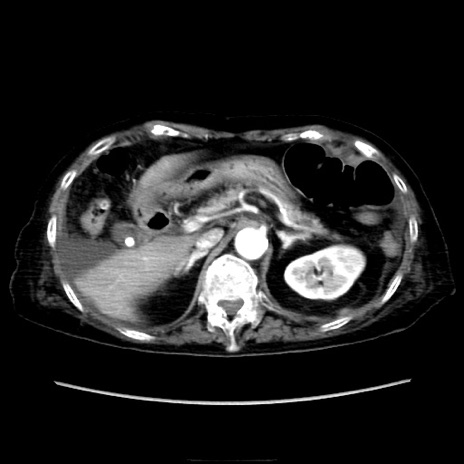

症例40(横断像)

横断像